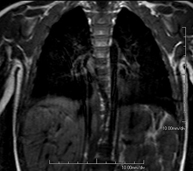

- Tòrax

- RM del Mediastí

Prova diagnòstica no invasiva que consisteix en l'obtenció d'imatges d'alta definició anatòmica del mediastí mitjançant l'ús d'un camp electromagnètic i ones de ràdio (amb un emissor i un receptor). No utilitza radiació ionitzant. El mediastí és la part central de la caixa toràcica que inclou el tim, els grans vasos (aorta toràcica, vena cava inferior i superior, etc.), el cor, la tràquea i els bronquis principals, els ganglis limfàtics mediastínics i hilars, l'esòfag, etc. Està especialment indicada en lesions mediastíniques per diferenciar si són quístiques o sòlides, en el diagnòstic diferencial de les lesions del mediastí anterior, etc. De vegades s'ha d'emprar contrast paramagnètic (Gadolini) per completar l'estudi. - RM Tòrax

Prova diagnòstica no invasiva que consisteix en l'obtenció d'imatges d'alta definició anatòmica del tòrax mitjançant l'ús d'un camp electromagnètic i ones de ràdio (amb un emissor i un receptor). No utilitza radiació ionitzant. Està indicada en aquelles lesions pulmonars en les quals s'ha de descartar si hi ha infiltració del mediastí o de la paret toràcica, per diferenciar si una lesió toràcica és sòlida o quística, etc. En alguns casos caldrà emprar contrast paramagnètic (Gadolini) per completar l'estudi. - RM de Paret Toràcica

Prova diagnòstica no invasiva que consisteix en l'obtenció d'imatges d'alta definició anatòmica de la paret toràcica mitjançant l'ús d'un camp electromagnètic i ones de ràdio (amb un emissor i un receptor). No utilitza radiació ionitzant. Està indicada en l'estudi de lesions de paret toràcica: costals, esternals, musculars (pectorals, intercostals, paravertebrals, etc.), en l'estudi de dolors costals, etc. En alguns casos caldrà emprar contrast paramagnètic (Gadolini) per completar l'estudi. - Angio-RM d'Aorta Toràcica